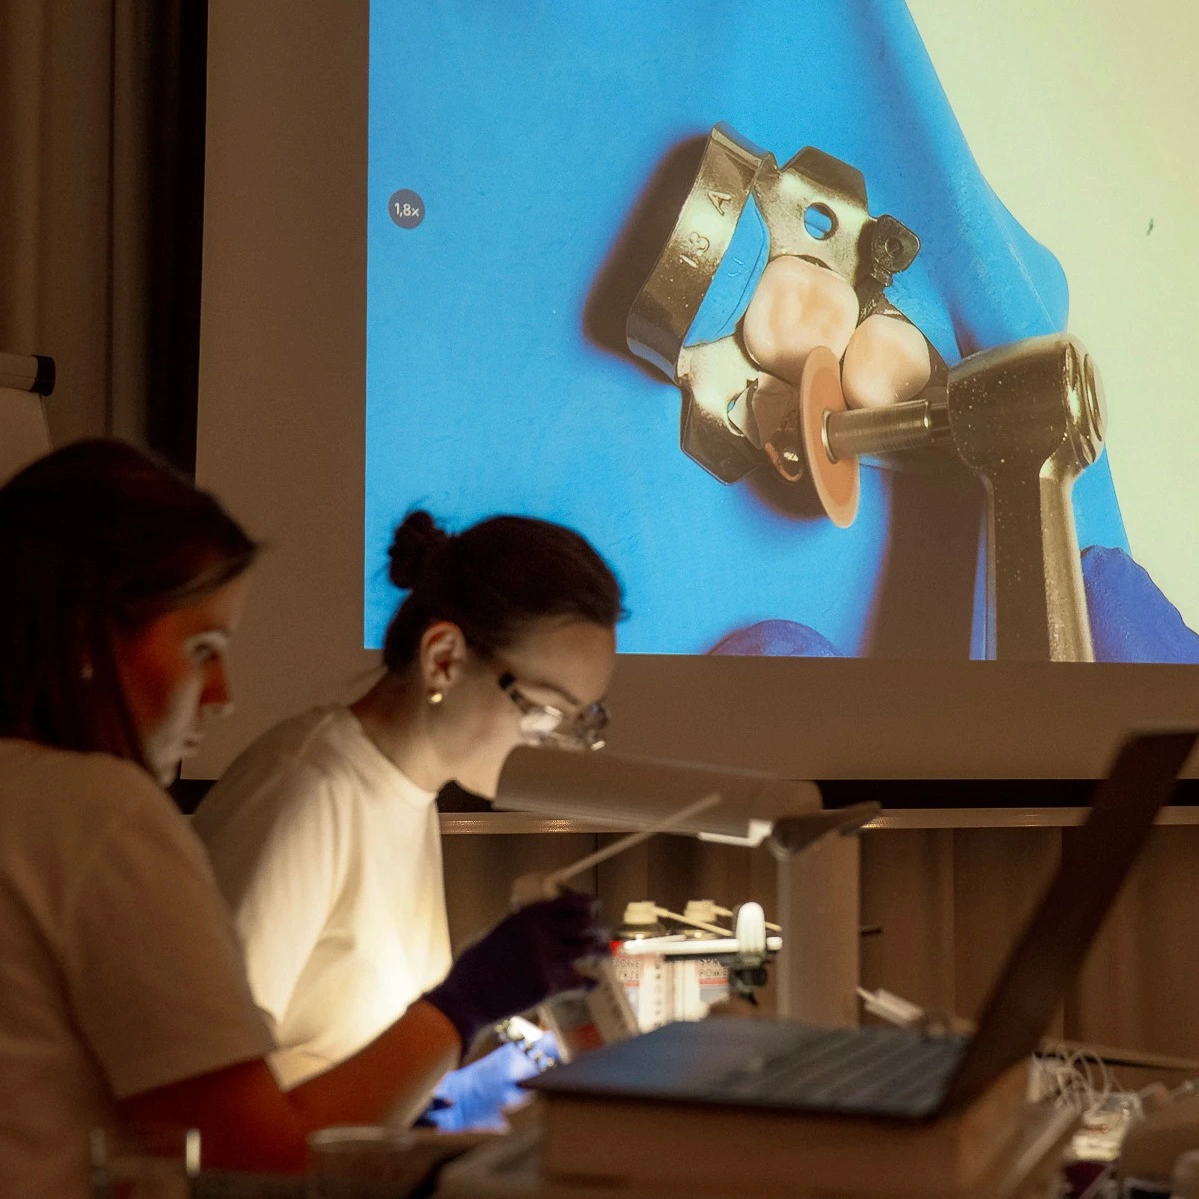

- leczenie w powiększeniu (lupy i mikroskop)

Prowadzimy szkolenia dla lekarzy z całej Polski w ramach kursów „Mleczaki bez tajemnic”, łącząc teorię z praktyką i omówieniem realnych przypadków klinicznych. Bierzemy aktywny udział w międzynarodowych konferencjach zarówno występując, jak i stale rozwijając nasze kompetencje.